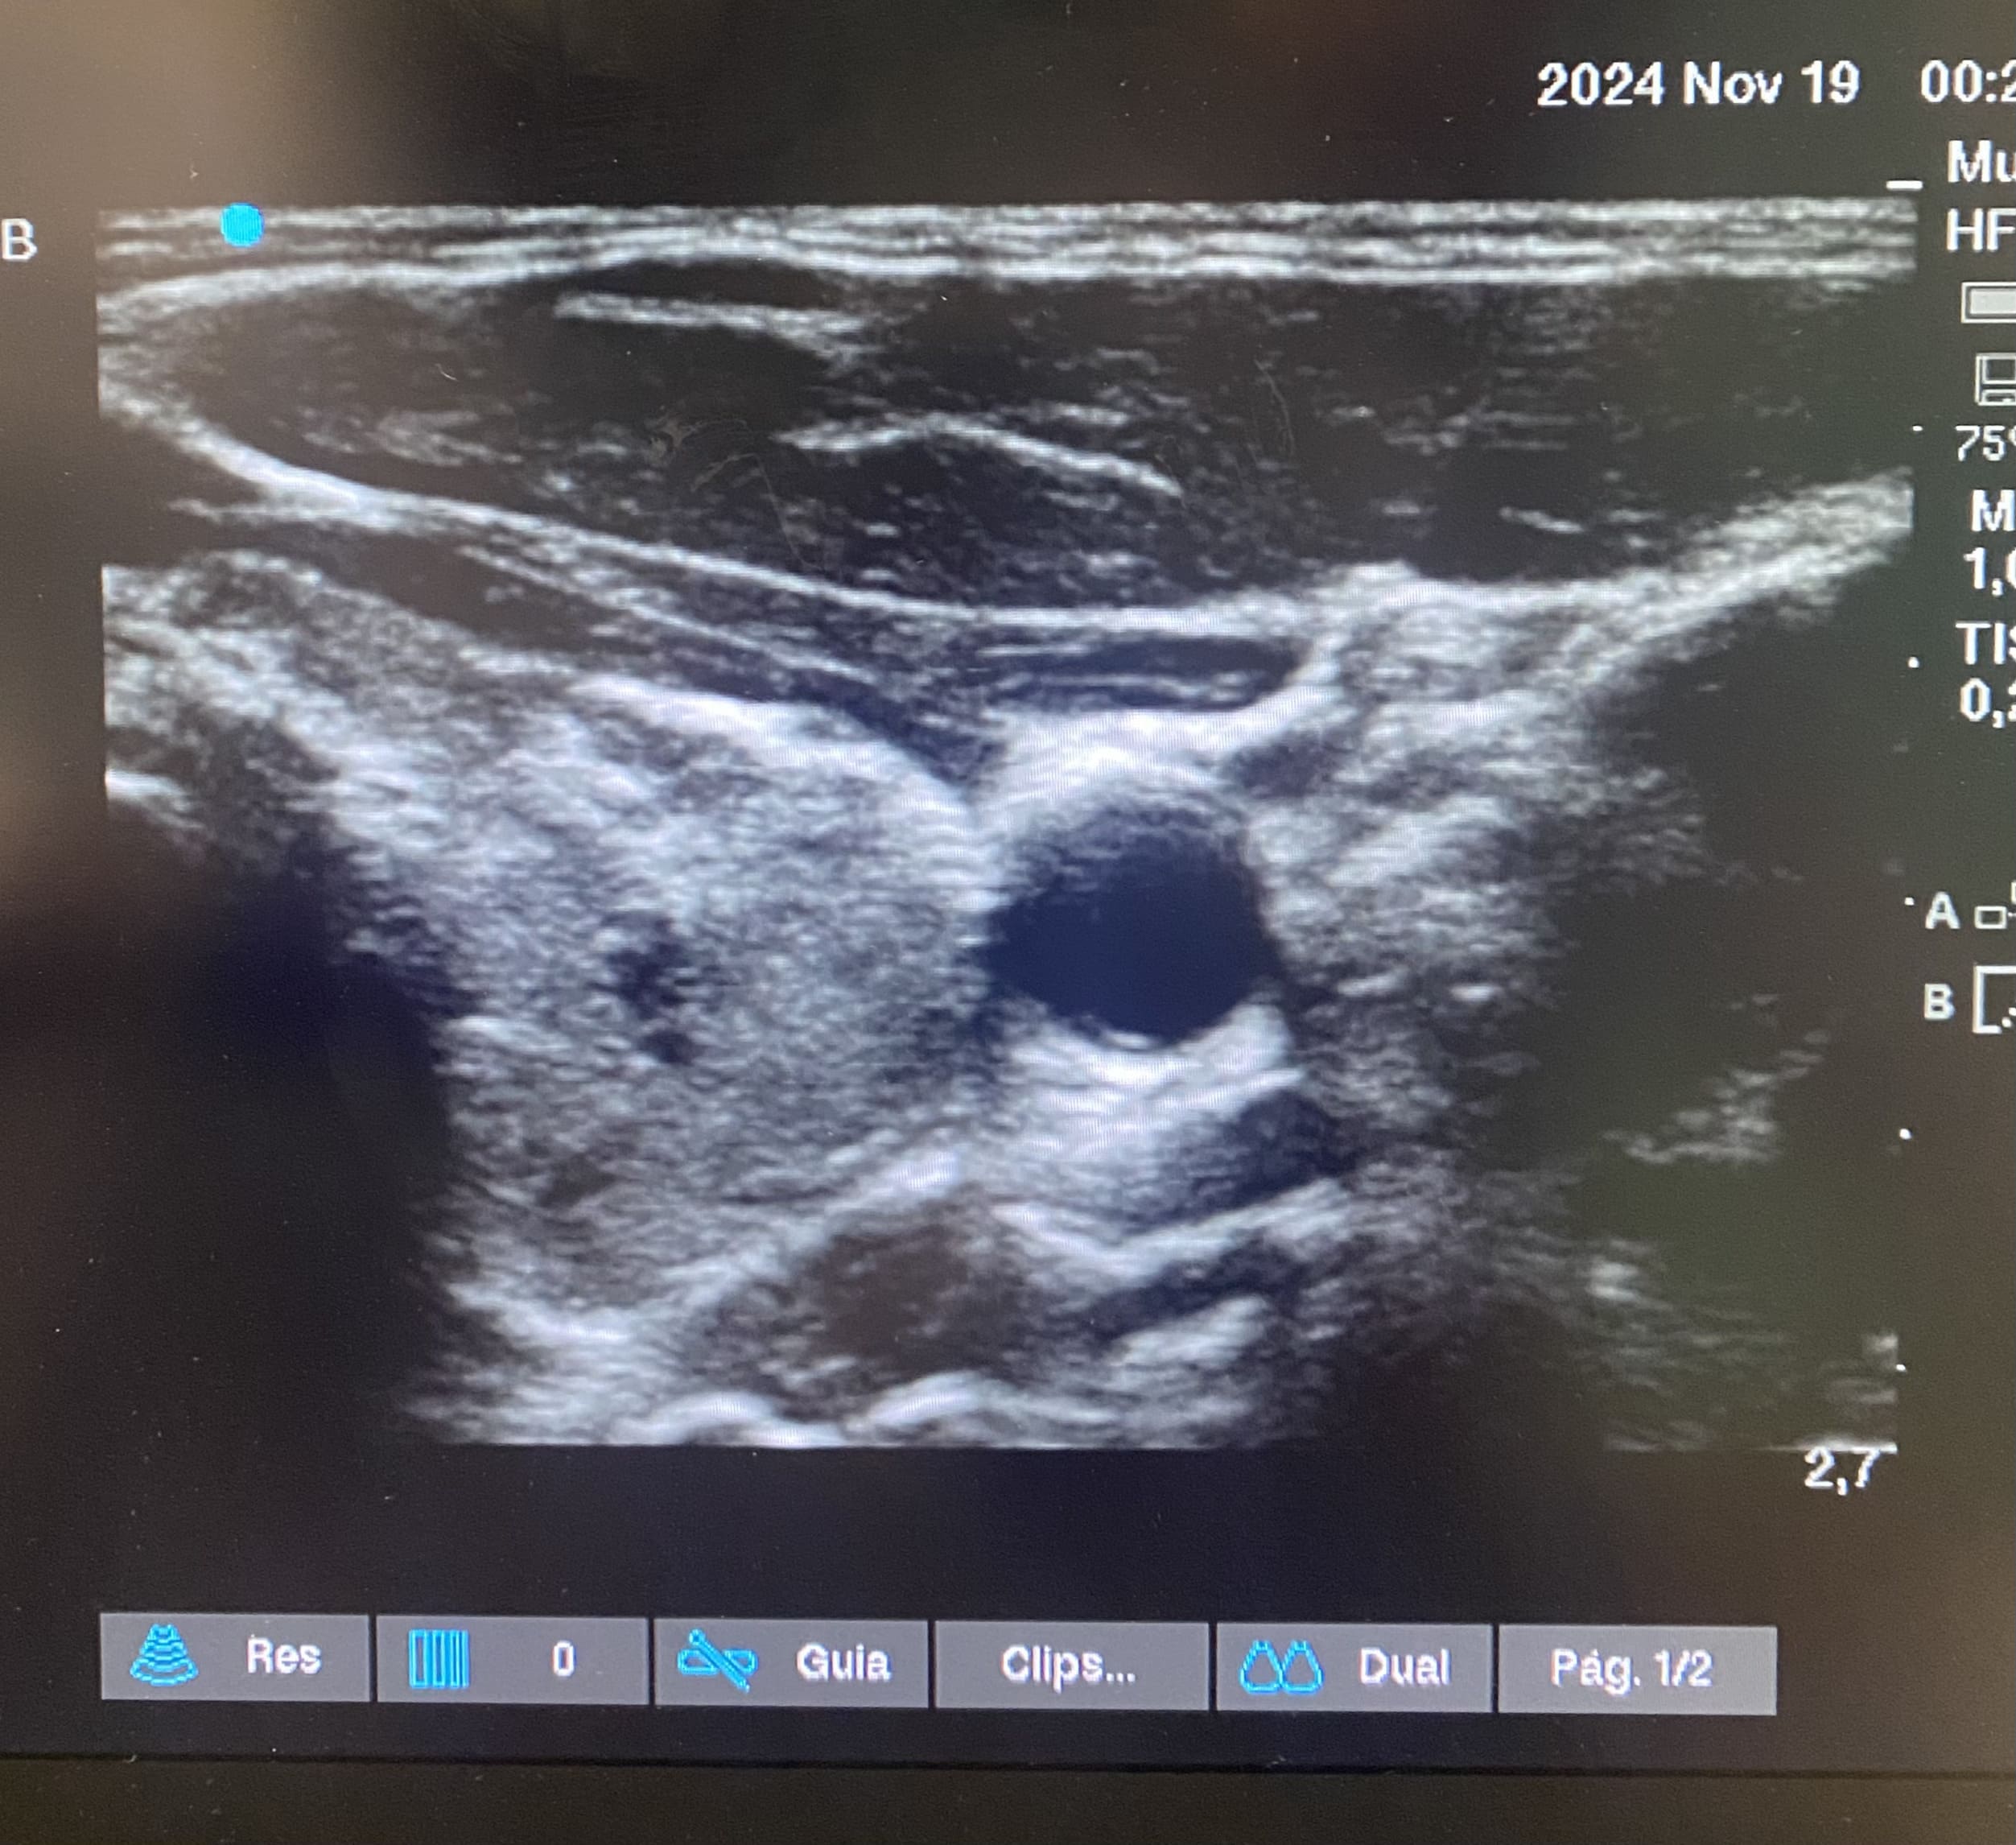

Planes de actuación: Se realiza ecografía en urgencias observándose glándulas tiroideas de tamaño normal con un patrón estructural alterado. Se inicia levotiroxina 50 mcg, se solicita ecografía reglada y anticuerpos (Ac) antitiroideos para control y seguimiento por su médico de atención primaria.

Ecografía de cuello-tiroides: Ambos lóbulos tiroideos presentan un tamaño dentro de la normalidad, con contorno lobulado, ecoestructura muy heterogénea con áreas seudonodulares y septos fibrosos y alguna pequeña formación quística. Hallazgos compatibles con tiroiditis probablemente autoinmune (valoración clínica y analítica).